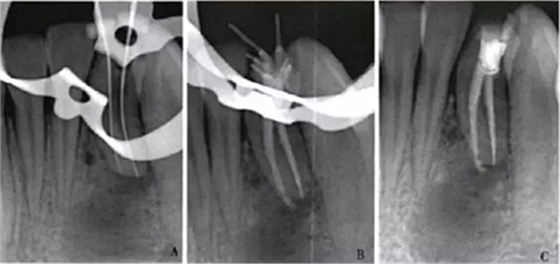

1周后,患者述疼痛消失。復(fù)診采用冷測壓方法根管充填(圖2),牙冠開髓孔處應(yīng)用Chem—flex(DentsplyDeTreyGmbH,Konstanz,Germany)充填。由于患牙牙冠形態(tài)異常,且唇側(cè)形態(tài)尚未恢復(fù);患牙周圍有牙石、軟垢,建議患者行牙周及修復(fù)治療以維持長期療效,被患者拒絕。9個(gè)月后隨訪,患者自述患牙經(jīng)治療后無癥狀,臨床檢查見32叩診正常,無松動;影像學(xué)檢查見32根尖周圍透射區(qū)域明顯減?。▓D3)。

A:32術(shù)中片確定根管工作長度;B、C:32術(shù)后片示根管充填適充

圖2 32根管治療x線片